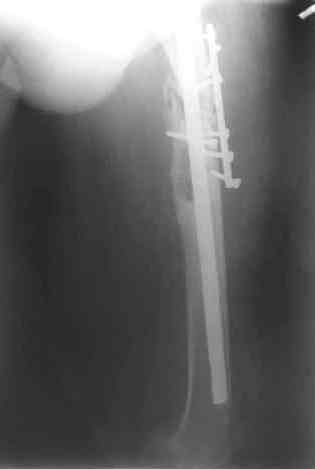

После нескольких некрэктомий, проведения аутодермопластики и заживдения ожоговой раны через 2 месяца после травмы произведен открытый остеосинтез левой бедренной кости штифтом и пластиной (деротационной) [image 01, 02]. Через 1 год и 7 месяцев после травмы у больного диагностированы ложный сустав и хронический остеомиелит левой бедренной кости. Произведено удаление металлических фиксаторов, секвестрэктомия и остеосинтез бедренной костивнешним двухплоскостным стержневым аппаратом [image 03, 04] .

Через 3 года после травмы констатировало отсутствие консолидации бедренной кости, сохранение признаков хронического остеомиелита (свищ в нижней трети левого бедра). Произведен демонтаж аппарата, реостеосинтез бедренной кости спице-стержневым аппаратом, некрсеквестрэктомия. В аппарате удалось лишь частично произвестиустранение углообразной деформации бедренной кости [image 05] .

Через 4,5 лет после травмы выявлены рентгенологические признаки консолидации перелома, признаки хронического остеомиелита купировались. Аппарат был демонтирован. Пациент продолжил ходьбу с дозированной нагрузкой на конечность при помощи костылей. Через 2 месяца начал ходить при помощи трости. Однако, еще через 2 месяца отметил появление свищей на бедре с гнойным отделяемым и укорочение длины конечности. При осмотре в январе 2007 г.: пациент ходит при помощи костылей без опоры на левую нижнюю конечность, на бедре имеются множественные рубцы, на наружной поверхности сегмента в верхней и нижней третях имеются два свищевых хода со скудным серозно-гнойным отделяемым; отечности тканей конечности нет, пальпация безболезненная, отмечается укорочение длины конечности на 5 см, патологическая подвижность не определяется, имеется стойкая разгибательная контрактура коленного сустава (разгибание - 180 гр, сгибание - 170 гр), признаков нарушения кровоснабжения и иннервации тканей конечности нет. Температура тела нормальная. В общих анализах крови и мочи отклонений от нормы нет. [image 06,07, 08 (стрелками отмечены свищевые раны, 09, 10]Дорогие коллеги, я уверен, что у многих из вас после знакомства с данным клиническим наблюдением появится множество вопросов, касающихся уже проведенного лечения (особенно, сроков и способов). Сразу оговорюсь - я не смогу правильно ответить на многие вопросы (особенно касающиеся предшествующего периода лечения). Прошу вас, конечно по возможности, сосредоточить внимание не на разборе допущенных ошибок (проведенного лечения), а помочь добрым советом относительно тактики наших дальнейших действий. Наверное, кто-то располагает бесценным опытом лечения подобной патологии.